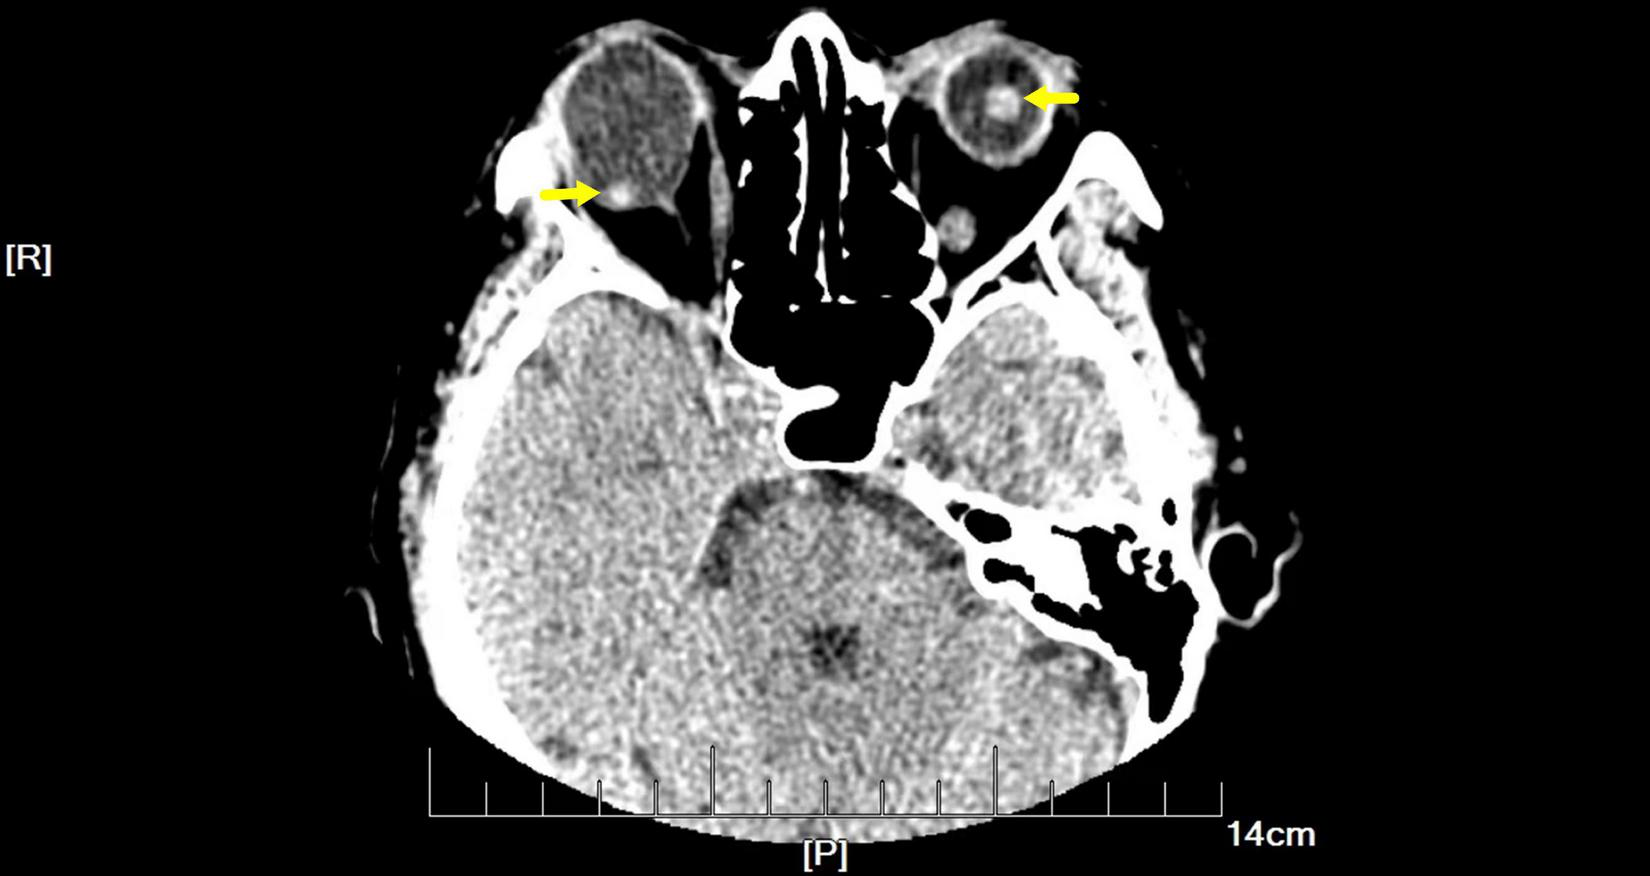

FIGURE 2

Orbital computed tomography (CT) demonstrated free-floating lenses in the posterior poles (yellow arrows).

On examination, her height and weight were 165 cm and 66.2 kg, respectively. The best-corrected visual acuity was 20/300 OD and 20/250 OS, with a refractive status of +5.25/−2.75 × 25 OD and +5.75/−3.25 × 154 OS. The anterior segment showed the absence of lenses in both eyes. Fundus examination revealed optic atrophy, staphyloma, and chorioretinal atrophy. The initial intraocular pressure was 16 mm Hg OD and 17 mm Hg OS, and the axial length was 31.11 mm OD and 29.33 mm OS. B-ultrasound showed that the lenses were located in the vitreous cavity in both eyes (red arrows, Figure 1). Orbital computed tomography (CT) demonstrated free-floating lenses in the posterior poles (yellow arrows, Figure 2), and spectral-domain optical coherence tomography (SD-OCT) revealed a lamellar macular hole and retinoschisis in the right eye (Figure 3).